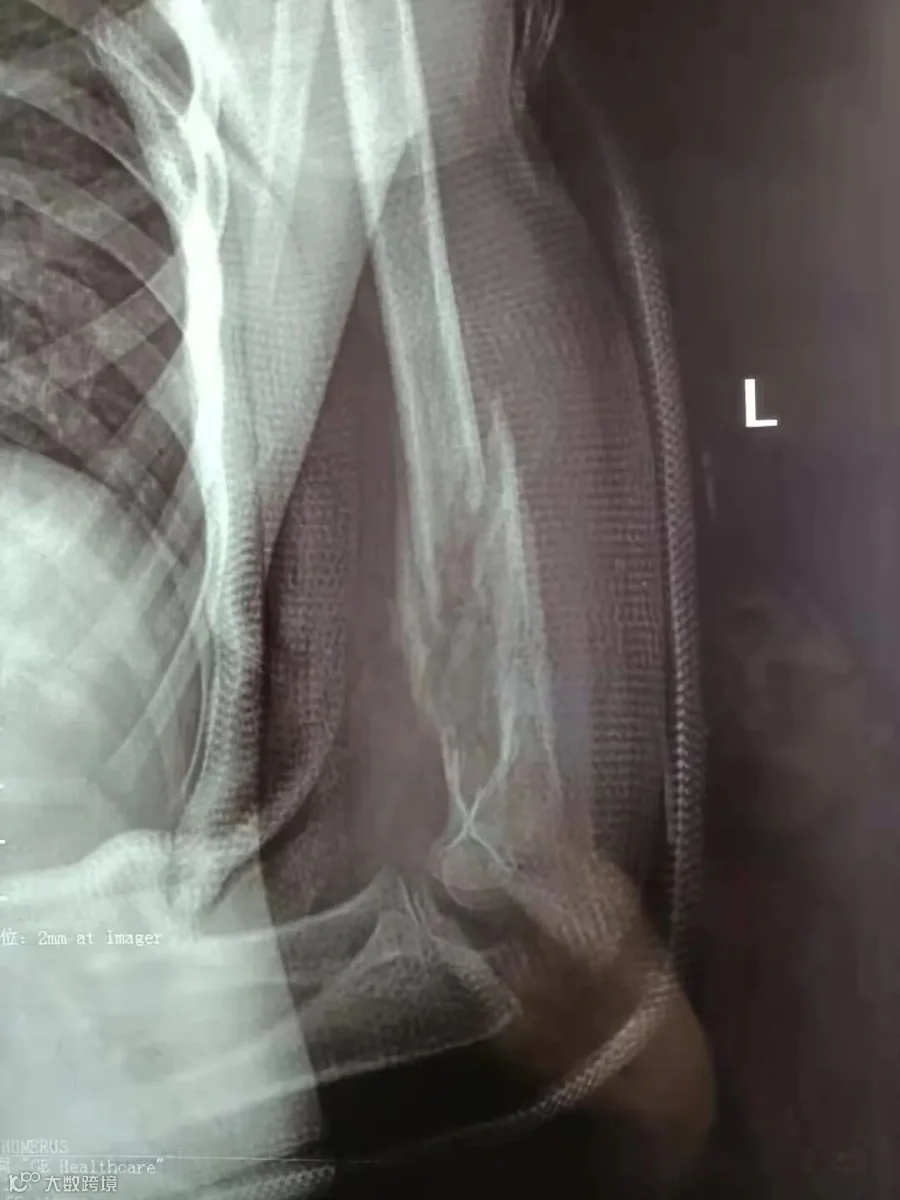

韦韦(化名),6岁8个月

治疗前